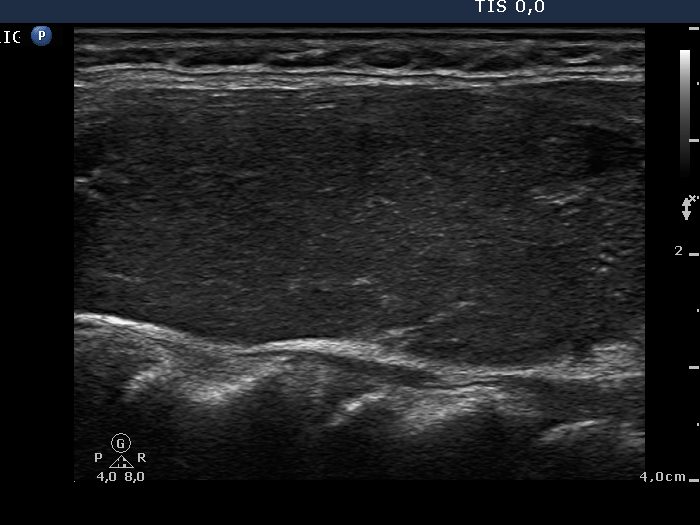

Graves' disease - Case 1289 (ultrasonographic picture 5)

Left lobe, longitudinal scan.